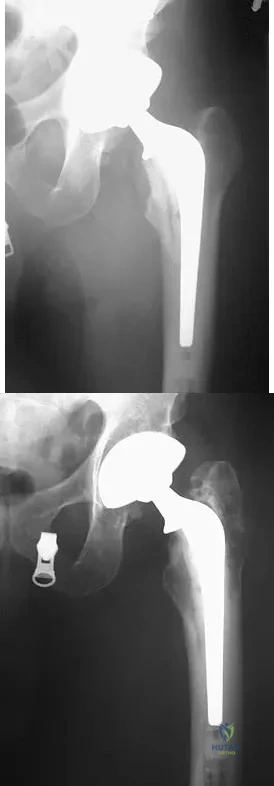

A patient who underwent primary total hip arthroplasty 7 years ago that resulted in excellent pain relief and a normal gait now reports pain and a limp. Postoperative and current AP radiographs are shown in Figures 2a and 2b. What is the most likely cause of the pathology seen?

Explanation